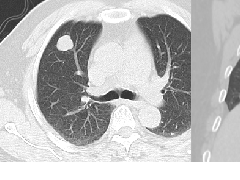

肺段与肺内管道应用解剖  肺转移瘤的十种不典型CT表现

肺转移瘤的十种不典型CT表现  肺内淋巴结的CT表现特点及与病理对照

肺内淋巴结的CT表现特点及与病理对照  肺实变与肺不张的CT鉴别诊断